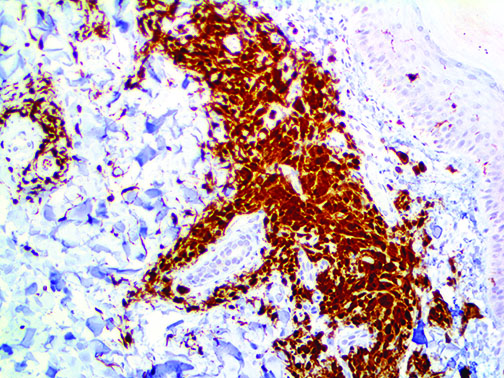

It is the ICU physician who is most likely to witness one of the deadliest manifestations of the abnormal immunological response, the cytokine storm syndrome (CSS). This response is also referred to by some as the cytokine release syndrome (CRS). CSS is characterized by continuous activation and expansion of macrophage and lymphocyte populations, which secrete large amounts of cytokines, causing the cytokine storm. This massive cytokine release is akin to hemophagocytic lymphohistiocytosis (HLH) disease, a syndrome characterized by initial unchecked and persistent activation of cytotoxic T lymphocytes and NK cells.

Clinical and laboratory manifestations of HLH include fever, enlarged liver and/or spleen, neurologic dysfunction, coagulopathy, liver dysfunction, cytopenias (i.e., low levels of erythrocytes, leukocytes, and/or platelets), hypertriglyceridemia, hyperferritinemia, hemophagocytosis, and eventually diminished NK cell activity as the immune system becomes progressively paralyzed. HLH can be familial (primary HLH) or secondary to another disease process (sHLH), such as rheumatic disease, in which it is referred to as macrophage activation syndrome (MAS, characterized by elevated ferritin).

This activation induces inflammatory monocytes to highly express IL-6, starting a localized and then systemic cascade effect that results in hyperproduction of IL-6, which accelerates the inflammatory process. Because IL-6 also increases vascular permeability, excessive levels cause blood vessels to become very leaky. This, along with clotting factors released from vascular endothelial cells, stimulates the coagulation cascade, resulting in microthrombosis (tiny clots), which leads to ischemia and tissue death of the kidney, intestines, heart, liver, brain and extremities.